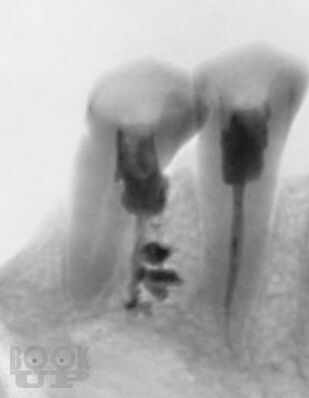

В учебно-методическом пособии представлены существующие классификации ошибок при лечении осложненного кариеса зубов. Проанализированы основные причины, приводящие к возникновению ошибок при диагностике, механической и медикаментозной обработке и обтурации корневых каналов. Рассмотрены методы предупреждения наиболее часто встречающихся осложнений эндодонтического лечения.